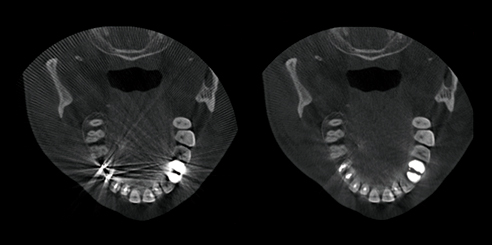

T-MAR Metal Artifact Reduction in LargeV Dental CBCT

With the new T-MAR module, the system automatically removes metal artifacts and corrects image distortions intelligently.

Hence, the final images remain clear, accurate, and clinically reliable.